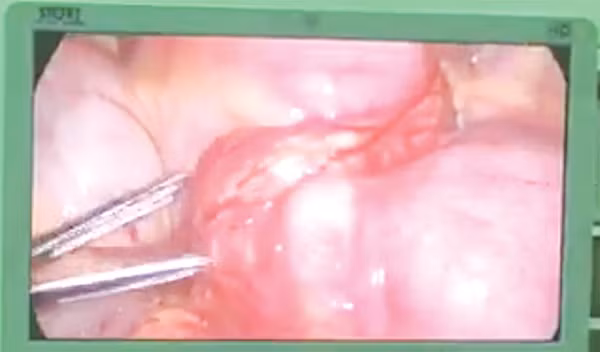

Ca phẫu thuật nội soi gắp dị vật

Sau khi chụp CT-scan ổ bụng cho người bệnh, các bác sĩ Khoa Ngoại Tiêu hóa BV. ĐHYD phát hiện một chiếc tăm dài khoảng 6cm đâm thủng ruột non, tạo khối ápxe trong ổ bụng. Em S. không nhớ mình nuốt tăm khi nào, có lẽ trong một lần ăn bún thịt nướng. Người bệnh lập tức được phẫu thuật nội soi lấy dị vật và cắt bỏ đoạn ruột bị thủng kèm khối ápxe quanh dị vật. Sau đó, toàn bộ khối này được đưa ra ngoài qua lỗ mở bụng nhỏ 4cm. Vì được phát hiện và phẫu thuật lấy dị vật kịp thời bằng phương pháp xâm lấn tối thiểu, nên sau mổ người bệnh phục hồi nhanh, có thể ăn uống, sinh hoạt như bình thường và xuất viện sau 5 ngày. Em S. được hẹn tái khám sau 2 tuần để chắc chắn không còn tình trạng viêm nhiễm trong ổ bụng cũng như tại vết mổ. Sau đó, em sẽ được phẫu thuật điều trị bệnh tim của mình.